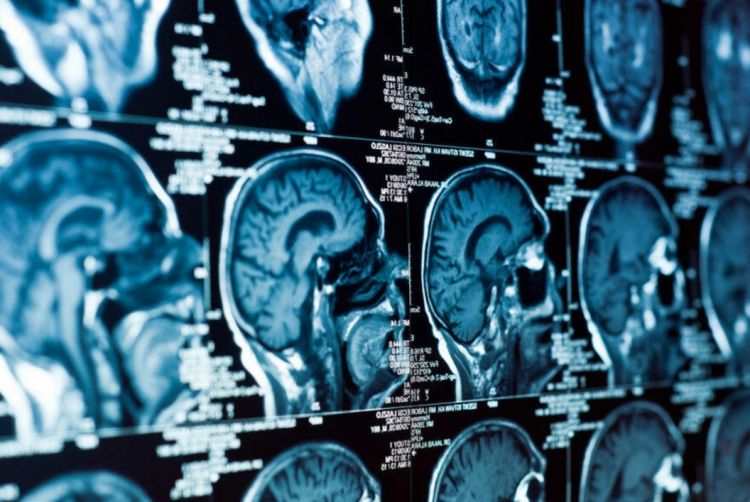

"Weill Cornell" Tibb Kollecinin (WCMC-Q) alimləri müəyyən ediblər ki, CT scan avadanlığı və qan laxtalanmasına qarşı dərmanlarla təchiz edilmiş mobil təcili yardım otaqları bir çox insultların qarşısını ala bilər və insult keçirən insanların sağ qalma nisbətini yaxşılaşdıra bilər.

2014-cü ildən 2020-ci ilə qədər yüksək keyfiyyətli tədqiqatların məlumatlarından istifadə edərək, yeni məqalənin müəllifləri insult şübhəsi olan 1009 xəstənin məlumatlarını təhlil ediblər: 644-ü mobil təcili yardım şöbəsində, 365-i isə xəstəxanada laxta həlledici dərman (toxuma plazminogen aktivatoru) qəbul edib. Xəstələrə insult əlamətlərinin başlanmasından orta hesabla 87 dəqiqə sonra qayğı göstərilib.

Səyyar təcili yardım şöbəsinə müraciət edən xəstələrə orta hesabla 37 dəqiqə tez qulluq göstərildiyi üçün bu qrupda daha çox insultun qarşısı alınıb. Ən yaxşı nəticələr simptomların başlanmasından sonra ilk 45 dəqiqə ərzində qayğı alan xəstələrdə müşahidə edilib.